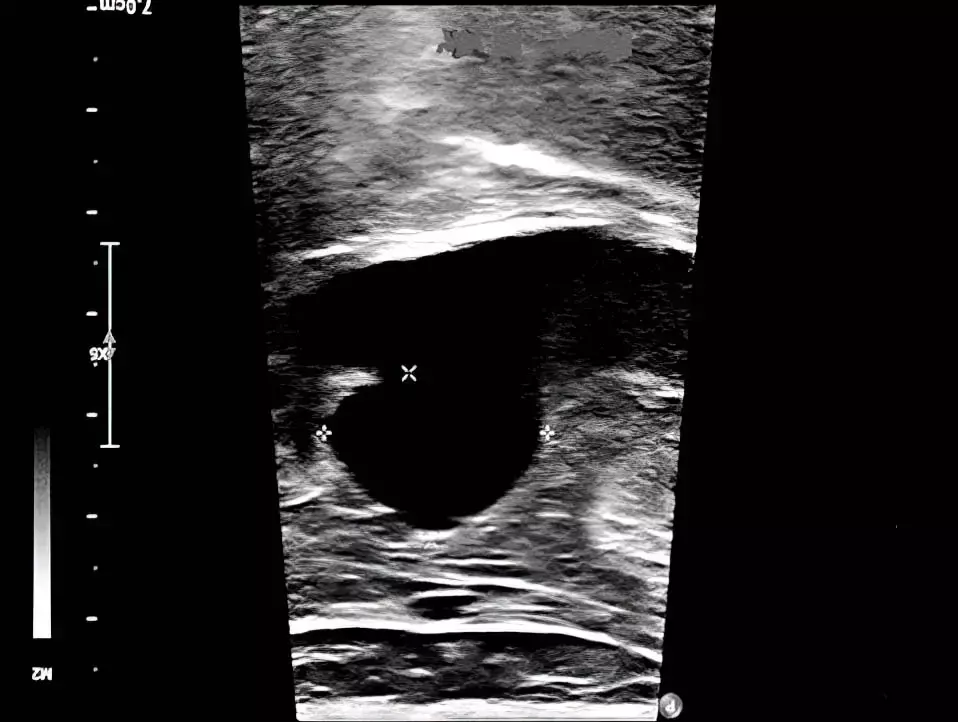

Рисунок 1. УЗ-верификация аневризмы подколенной вены.Основным методом диагностики аневризмы подколенной вены является ультразвуковая верификация, позволяющая выявить патологию на ранних этапах, оценить диаметр подколенной вены, ее анатомические изменения и характер кровотока (см. рис. 1).

paiicyifc5Рисунок 3. Аневризма подколенной вены диаметром 32×42 мм на УЗИ.По данным УЗИ выявлена аневризма проксимальной части подколенной вены диаметром 32×42 мм, с турбулентным кровотоком в полости аневризмы и эффектом спонтанного контрастирования (см. рис. 3).